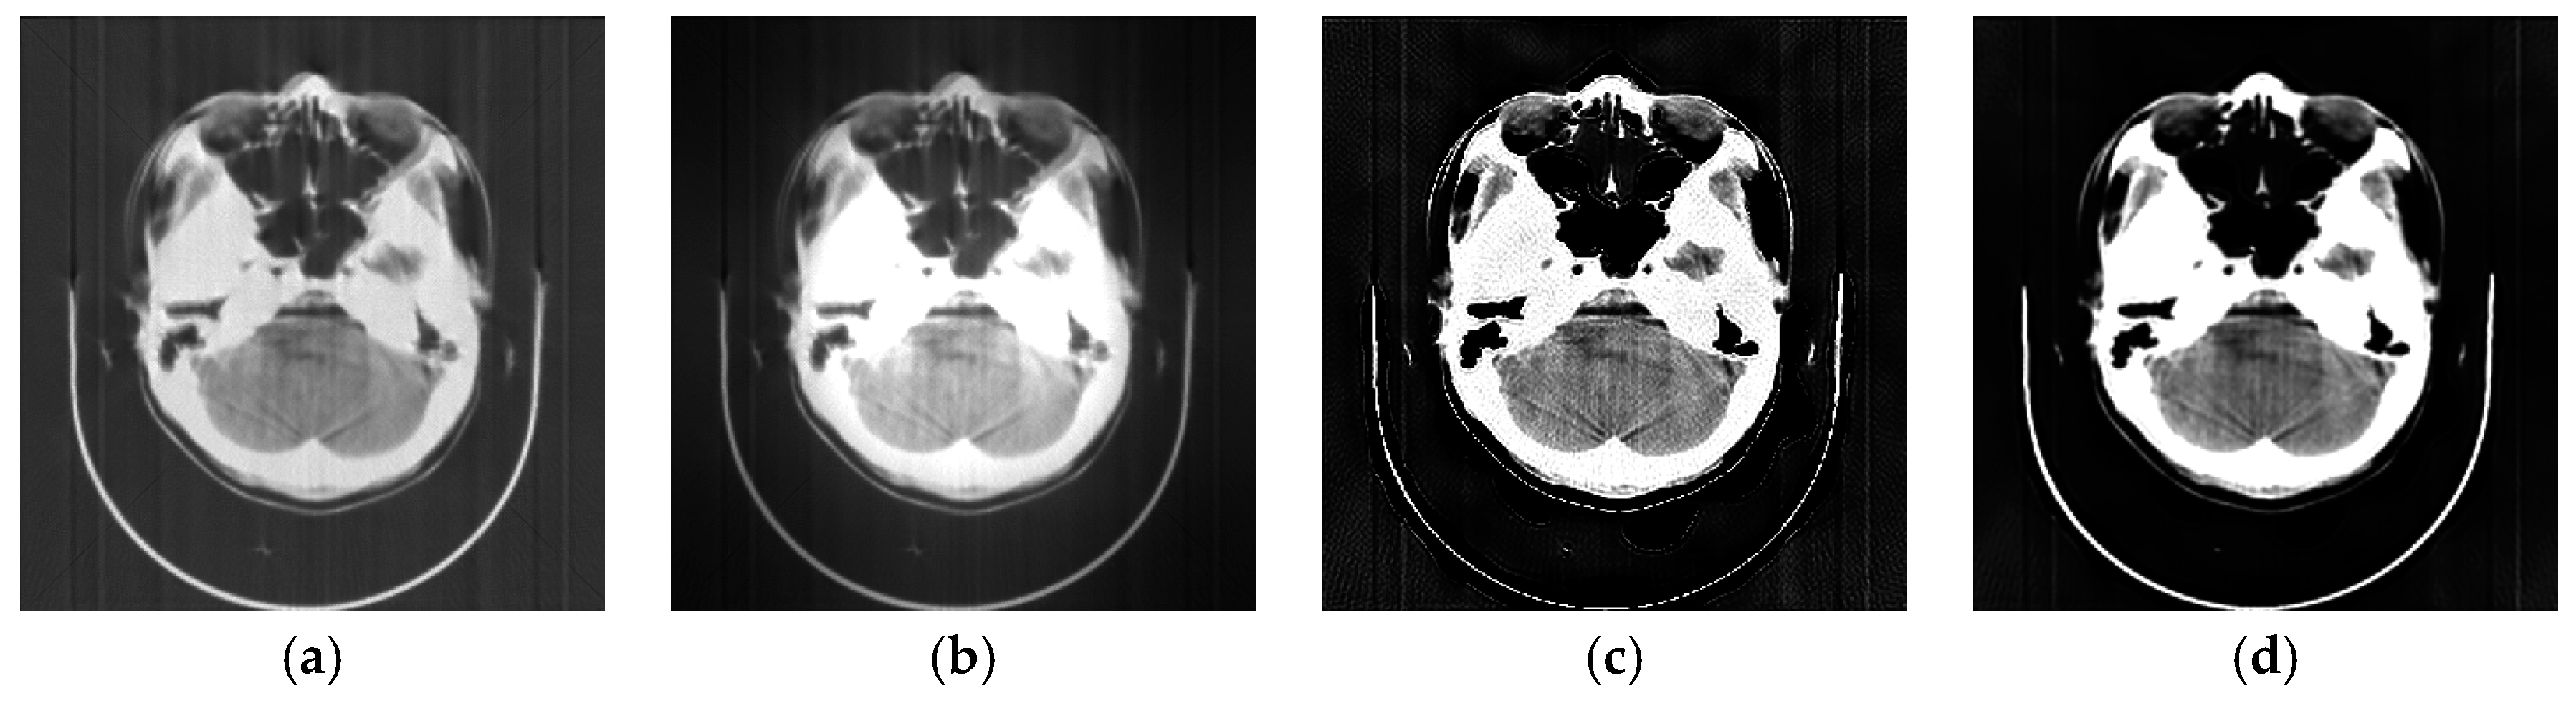

Diagnostics Free FullText AutoDetection of Motion Artifacts on CT Patient Motion Artifact Ct Patient motions commonly have a component. They are caused by patient movement during. Motion artifacts are a common problem in computed tomography (ct) imaging. Motion artifacts in ct imaging can be caused by voluntary or involuntary patient movement such as swallowing during the scan acquisition. Ct artifacts can be classified according to the underlying cause of the artifact. Patient Motion Artifact Ct.

Algorithms Free FullText A Rigid Motion Artifact Reduction Method Patient Motion Artifact Ct Motion artifacts in ct imaging can be caused by voluntary or involuntary patient movement such as swallowing during the scan acquisition. They are caused by patient movement during. Patient motions commonly have a component. Motion artifacts are a common problem in computed tomography (ct) imaging. Ct artifacts can be classified according to the underlying cause of the artifact. Patient Motion Artifact Ct.

Algorithms Free FullText A Rigid Motion Artifact Reduction Method Patient Motion Artifact Ct Ct artifacts can be classified according to the underlying cause of the artifact. Patient motions commonly have a component. Motion artifacts in ct imaging can be caused by voluntary or involuntary patient movement such as swallowing during the scan acquisition. Motion artifacts are a common problem in computed tomography (ct) imaging. They are caused by patient movement during. Patient Motion Artifact Ct.